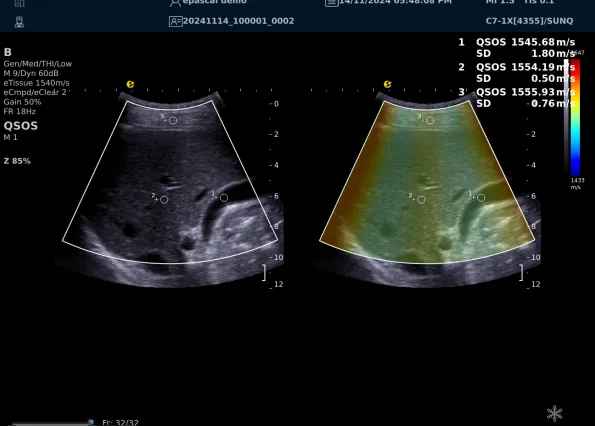

640.jpg123 (2).jpg可以设想,单位时间可发射的脉冲波越多、单位面积可发射的脉冲波越密集,得到的数据结果就越快、越多。也就是说,如果医生希望得到实时、大幅的声速定量图像,就需要超声系统具备“超快速”发射和接收的能力,新航娱乐医疗(ESI)ePascal东风系列超声平台的200+倍成像速度,成为了这项新技术得以临床应用的重要条件。

以上为应用声速定量成像技术检查肝脏的超声图像,图中在取样框内选择了三个测量区域,得出了各区域内的组织声速值以及声速衰减系数等结果。